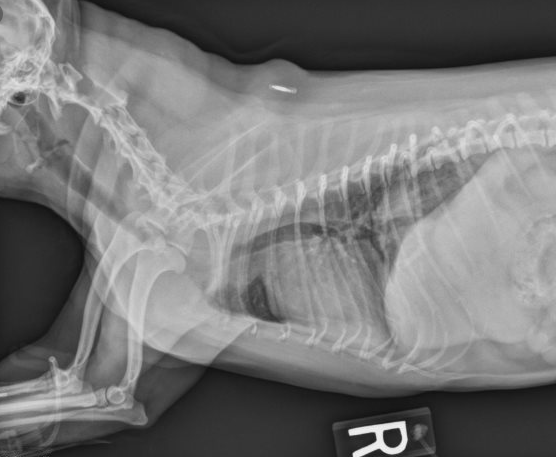

当饲主发现自己小狗又出现胸闷,牙龈转成蓝色时,应立玄带它带附近的宠物医院参与救治。规模很大宠物医院具备丰富的医疗配备,可向小狗需要提供氧气和那些治疗,以能减轻小狗的导致缺氧状况。当病情稳定后,兽医方可具体点为它并且诊断治疗。为了怎么分辨是气管下陷还是其他疾病影响到,兽医将首先咨询一饲主小狗以往的健康最好史。接下来的事情,诊断步骤也可以分成三类两部分,共有是:像是检查和影像检查。就像检查:实际喉部听诊可显现出出啰音。触诊检查时,是需要轻轻的的触碰气管,否则很容易直接导致窒息危险。心脏听诊时特别注意有无有充血性心衰。影像检查:X光片是最常用的方法。通常拍颈部、胸部侧位、肩臂位。如果不是在图像上看到气管变狭小,则可以通过检查诊断。狗的气管下陷也也可以实际内窥镜检查来明确诊断。内窥镜是一种医疗器械,其末端中有摄像头。但像X光片方法基本上是可以轻而易举察觉出问题在何处。什么是犬气管坍陷?有效预防和治疗很最重要 治疗方法才是关键(狗气管坍陷平时怎莫如何保养)(图6)影像检查结果